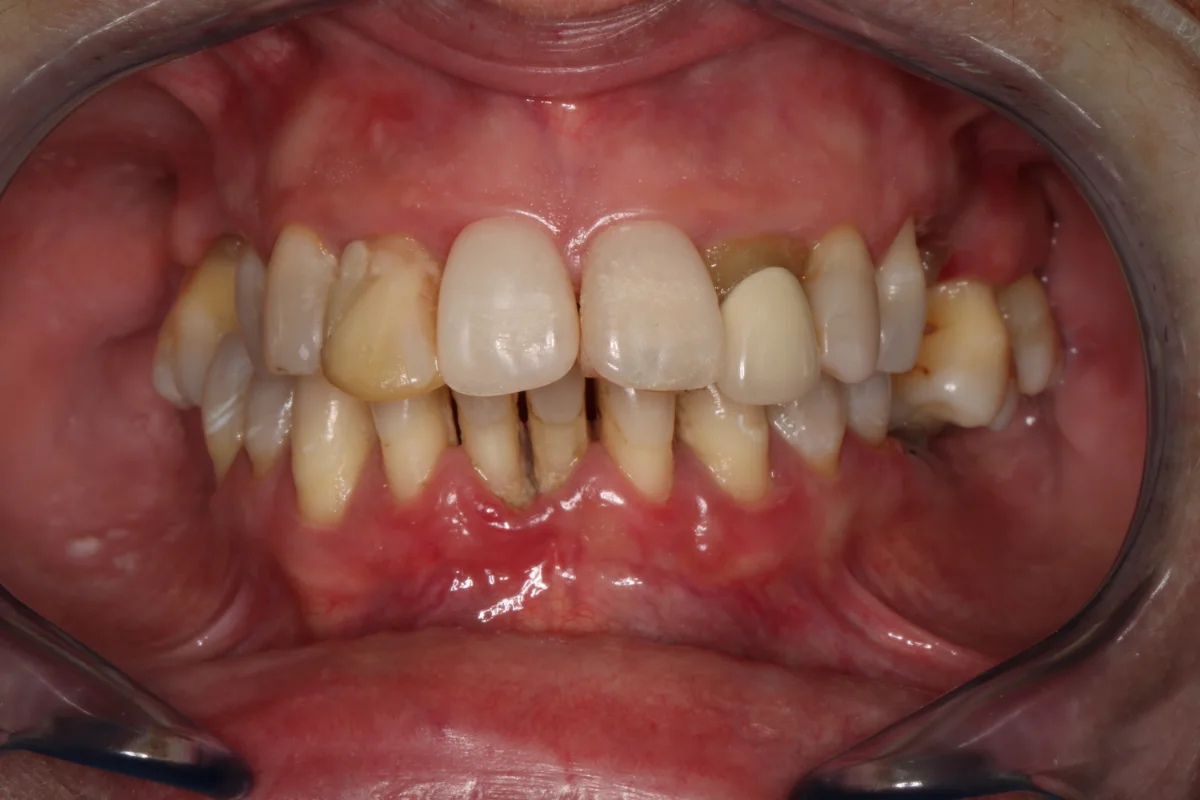

Siempre que el paciente reúna los requisitos clínicos adecuados, se irá con unas prótesis provisionales sobre los implantes que se colocarán en esa misma sesión.

Antes Antes